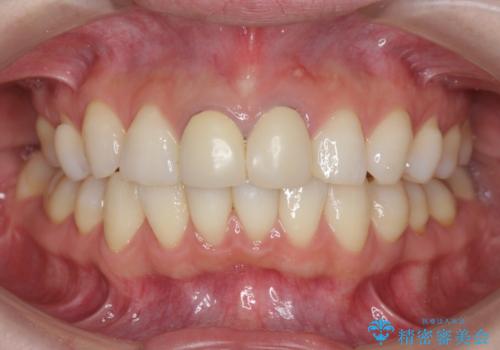

前歯が疼く セラミッククラウンのやり替え

- 「幼少期に転んで治療した前歯がうずく、疲れると膿が出る。」と治療を希望され来院されました。

X線写真検査に加え圧痛、打診痛が認められたため、慢性根尖性歯周炎と診断し、根管治療から行うセラミック治療を計画します。

今回は根尖性歯周炎に対する根管治療を行ったことで症状は改善し、快適に食事ができる状態へと改善しました。